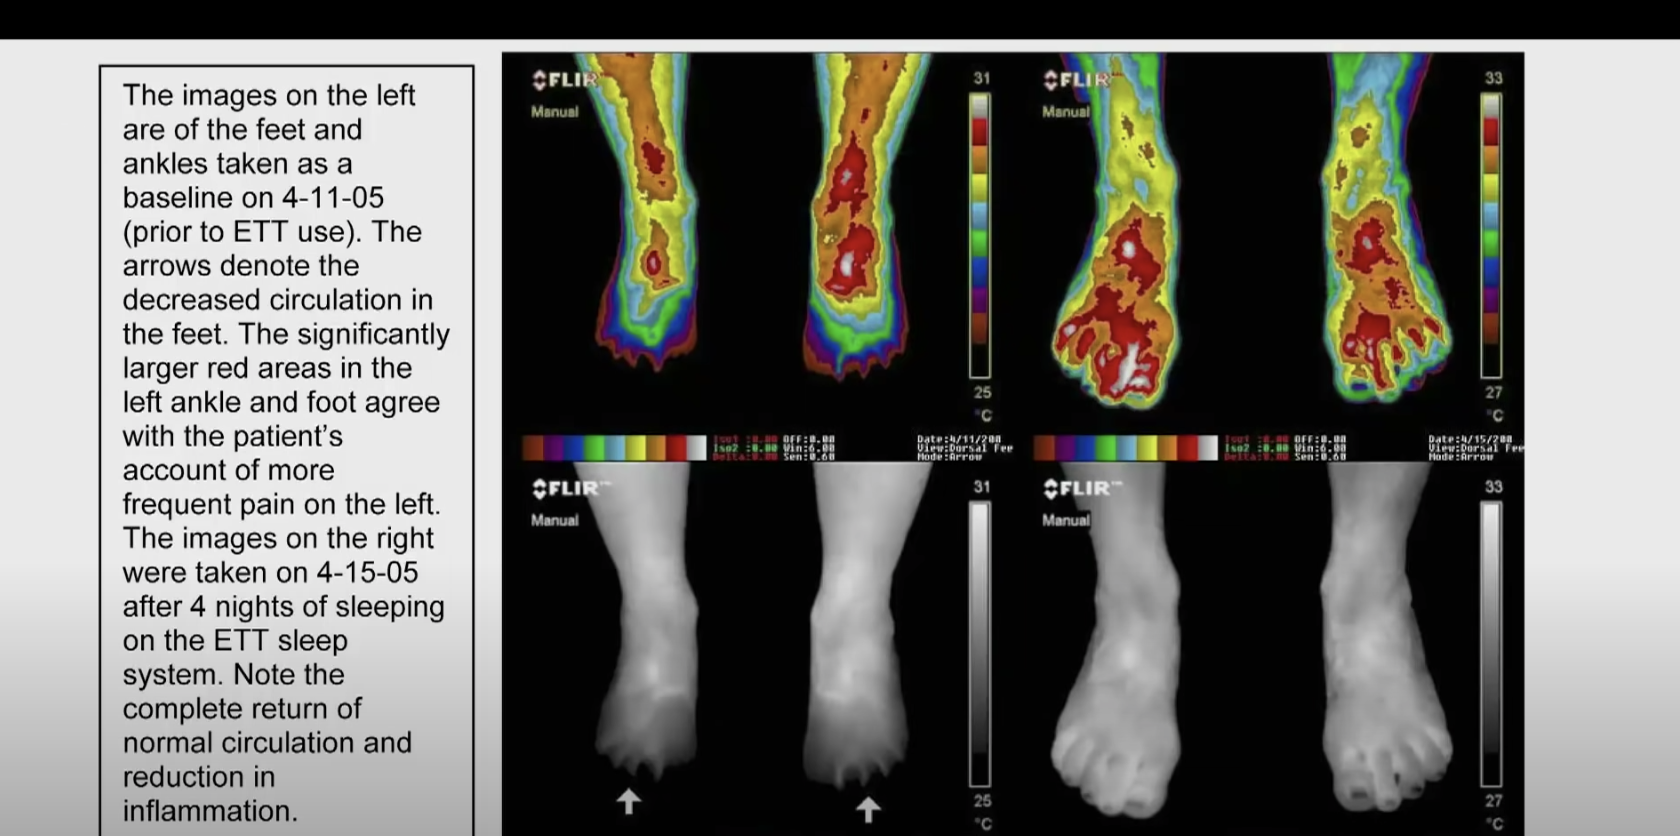

그러나, 인체를 접지한 경우에는 염증이 일어날 수 없습니다. 부족한 전자를 충분히 공급받을 수 있기 때문입니다. 접지를 하는 순간 인체 내의 전자는 순간적으로 포화됩니다. 너무 빨라서 측정이 불가합니다. 인체로 들어간 전자는 즉시 적혈구를 코팅하여 세포가 서로 밀어내게 만듭니다.

결과적으로 뭉치지 않게 만들어서 혈액의 점도가 낮아지고 심장이 혈액을 펌핑하기 용이하게 만들어 줍니다. 결과적으로 혈압이 강하하고 모든 종류의 심혈관 문제가 사라집니다. 혈액이 묽어지도록 만드는 것이 모든 생리학적 시스템의 균형을 이뤄내도록 만든다고 봅니다.